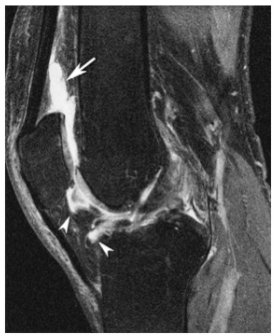

What is represented in this image?

A

Bone marrow lesions

What is the are the things indicated by the arrows and how does that influence OA?

That is infiltration of fragments of bone or cartilage into the synovium